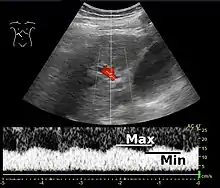

Increased blood pressure in the portal vein, called portal hypertension, is a major complication of liver disease, most commonly cirrhosis.[7] A dilated portal vein (diameter of greater than 13 or 15 mm) is a sign of portal hypertension, with a sensitivity estimated at 12.5% or 40%.[8] On Doppler ultrasonography, the main portal vein (MPV) peak systolic velocity normally ranges between 20 cm/s and 40 cm/s.[9] A slow velocity of <16 cm/s in addition to dilatation in the MPV are diagnostic of portal hypertension.[9]

Pulsatility

Portal vein pulsatility can be measured by Doppler ultrasonography. An increased pulsatility may be caused by cirrhosis, as well as increased right atrial pressure (which in turn may be caused by right heart failure or tricuspid regurgitation).[9] Portal vein pulsatility can be quantified by pulsatility indices (PI), where an index above a certain cutoff indicates pathology:

| Index | Calculation | Cutoff |

|---|---|---|

| Average-based | (Max - Min) / Average[9] | 0.5[9] |

| Max-based | (Max - Min) / Max[11] | 0.5[11][12] - 0.54[12] |